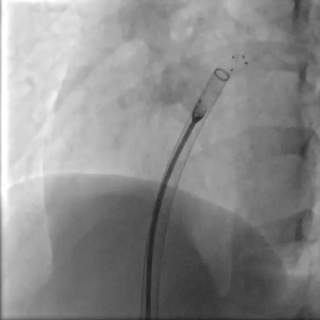

右盘展开

随后固定钢缆不动,回退鞘管,右盘展开

成型锁定

封堵器双盘扣合住间隔,鞘管抵住封堵器,前顶钢缆。助手固定钢缆和鞘管,牵拉成型线锁定

DSA可见Mark点聚集到一起,多普勒显示即刻阻流效果良好